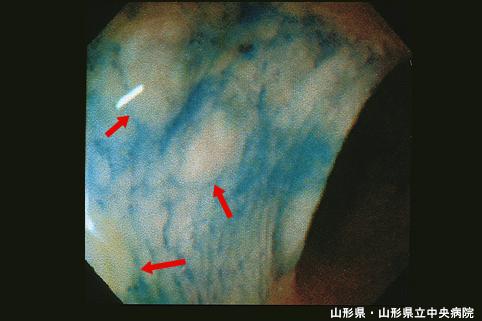

Múltiple Carcinoide del Recto de menos de 10 mm. acompañado de metástasis a ganglios linfáticos (Caso presentado por el Dr. Ikeda del Hospital Central Prefectural de Yamagata, prefectura de Yamagata)

[Image-ID:3973]

Now translating.